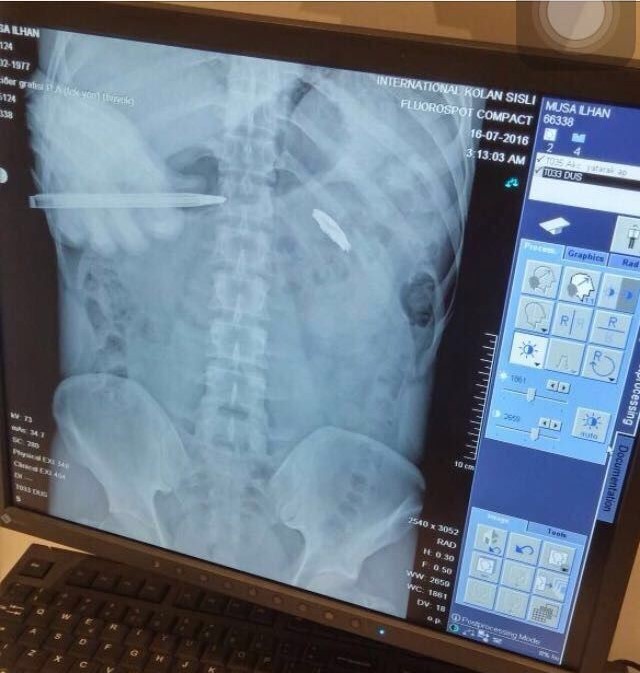

Fetullahçı Terör Örgütü’nün (FETÖ) 15 Temmuz 2016 tarihinde gerçekleştirdiği hain darbe girişiminin üzerinden 9 yıl geçti. Darbe girişiminde her yaştan vatandaş sokağa çıkarak darbeye ‘dur’ dedi. O vatandaşlardan kimi şehit oldu kimi de yaralanarak gazilik mertebesine erişti. Demokrasiye sahip çıkmak için sokağa çıkan Musa İlhan da darbeye karşı duranlardandı. İlhan, trafikte seyir halindeyken 15 Temmuz hain darbe girişimini radyodan öğrendi. Vatan savunması için sokakta kalan Musa İlhan, korkusuz bir şekilde darbeci askerlerin karşısına dikildi. Darbecilerin kurşunlarının hedefi olan İlhan, kalbinin 2 milimetre altına isabet eden mermiyle yere yığıldı. Ağır yaralanan İlhan, çevredekiler tarafından hastaneye kaldırıldı. 4 gün yoğun bakımda kalan İlhan, 2 ay süren tedavinin ardından sağlığına kavuştu. Ancak cerrahi müdahale riskli olduğu için kurşun çıkarılamazken, 9 yıldır hainlerin sıktığı mermiyle yaşıyor.